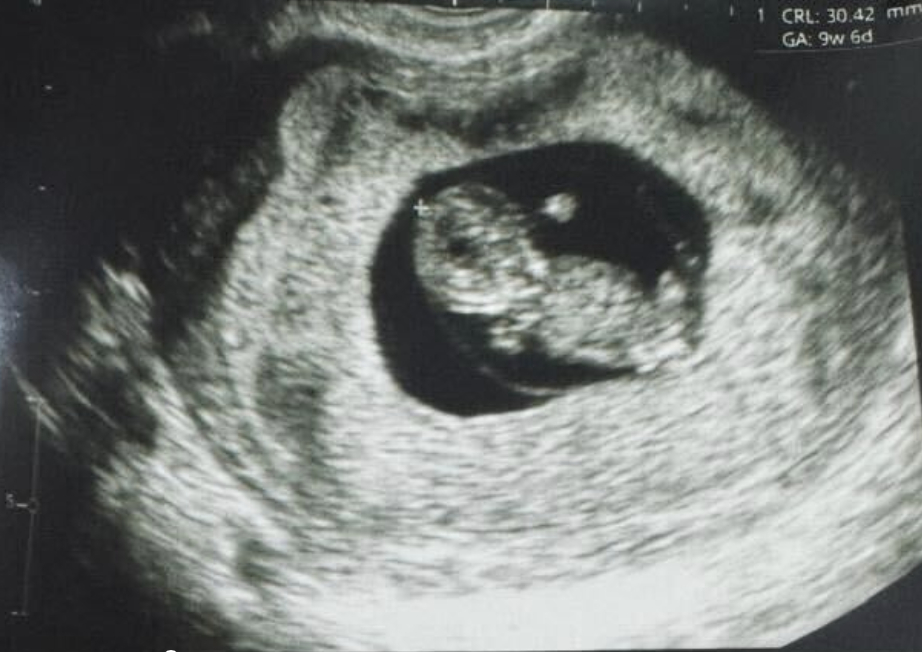

紐約(?BUSINESS WIRE?)致力于推動女性健康治療方案發(fā)展的生物技術(shù)公司Gameto與2024年12月16日宣布,該公司利用 Fertilo 實現(xiàn)了全球首例活產(chǎn)。此次分娩在秘魯利馬的圣伊莎貝爾診所進(jìn)行。